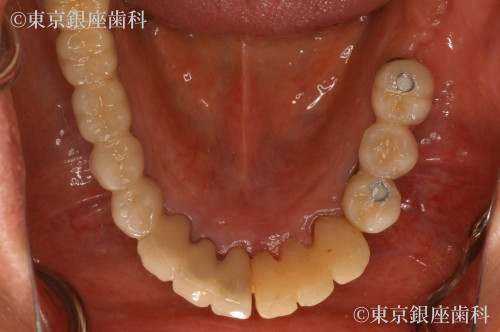

Before

奥歯上下をインプラント治療

奥歯は延長ブリッジ

糖尿病の為、血糖値を操作しオペを実施

糖尿病により血糖値が高い状態での手術はリスクを伴うため、事前に血糖値をコントロールしてインプラントを実施